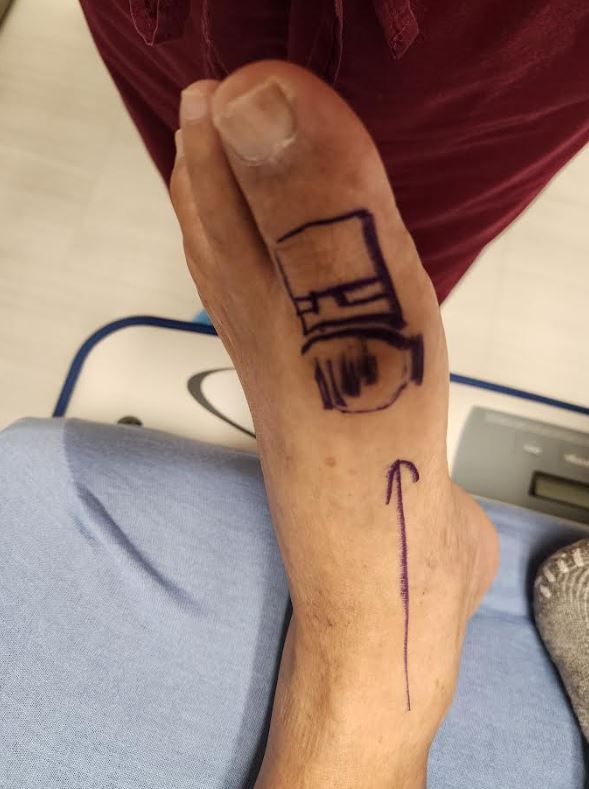

Hallux rigidus (arthritic great toe joint)

Hallux rigidus repair using the Regnauld technique, no metal or foreign body rejection. Immediate weight bearing and range of motion

Arthritic Joint Repair